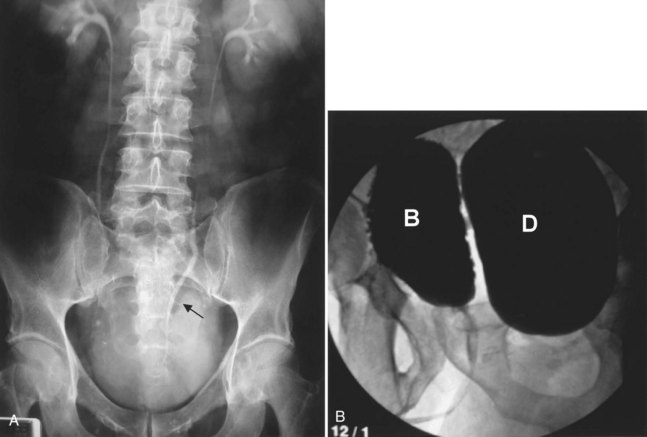

A bladder diverticulum may cause deviation with or without compression of the ipsilateral ureter. On intravenous urography, medial deviation of the pelvic ureter is most commonly seen; however, lateral deviation may also occur (Talner et al, 2000) (Fig. 78–5). Furthermore, a bladder diverticulum that encompasses the ureteral orifice may create a functionally shortened intramural ureteral segment and result in vesicoureteric reflux (see later discussion). In these patients, excision of the bladder diverticulum with ureteroneocystotomy may be necessary.

Figure 78–5 Bladder diverticulum with deviation of the ureter. This patient had a long history of recurrent urinary tract infections due to presumed prostatitis. A, 10-min film from the intravenous urogram demonstrating medial deviation of the pelvic ureter (arrow). B, Voiding image from the voiding cystourethrogram revealed a large, smooth-walled bladder diverticulum (D) emanating from the trabeculated bladder (B).